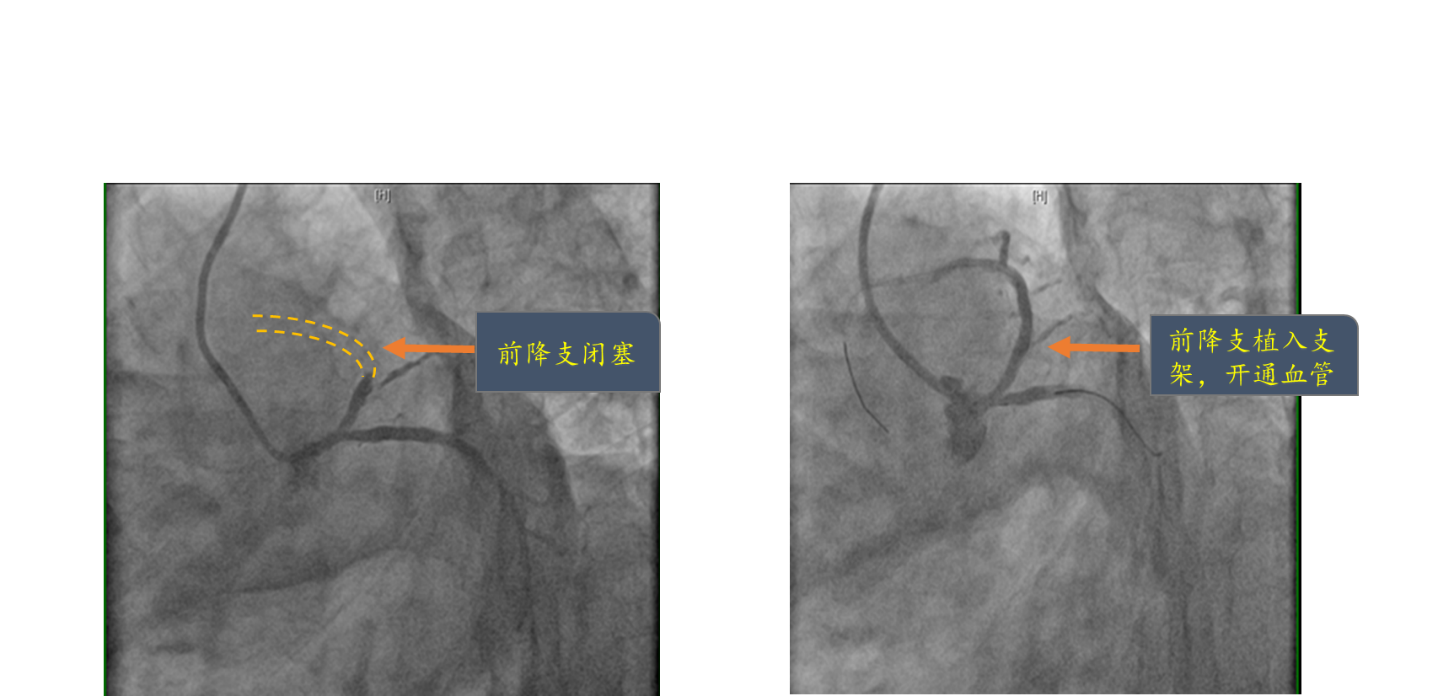

救护车转运过程中,北京清华长庚医院绿色通道已准备完毕,患者入院后直接接入心脏导管室,心脏内科介入团队迅速完成冠状动脉造影,术中可见患者供应心脏最主要的左前降支冠脉血管100%闭塞,使用球囊扩张开通闭塞血管,放置了一枚支架,永久性的开放闭塞血管。术后,苏先生被转运到心脏重症监护病房(CCU),6天后由CCU转至普通病房继续治疗。两周后苏先生完成心肌梗死后康复训练,恢复正常的日常生活运动,回家享受国庆假期。

左图显示前降支近段完全闭塞;右图显示植入支架后,前降支血流恢复正常